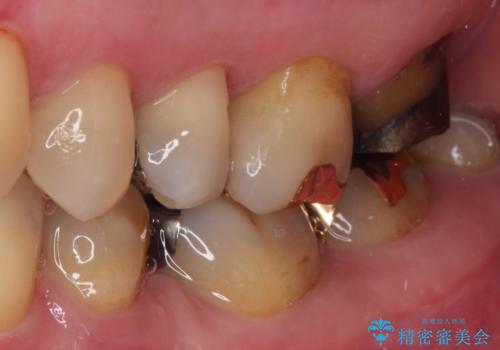

上の奥歯であることから、審美性よりも機能性を優先され、ゴールドクラウンを選択されました。

装着後の違和感など一切なく、見た目もほとんど気にならないとのことで、患者様には大変満足していただけました。